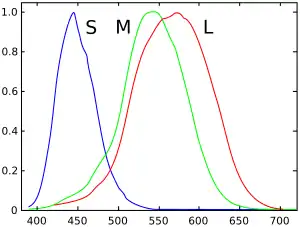

Las células sensoriales (fotorreceptores) de la retina que reaccionan en respuesta a la luz son de dos tipos: conos y bastones. Los bastones se activan en la oscuridad y solo permiten distinguir el negro, el blanco y los distintos grises. Nos permiten percibir el contraste. Los conos, en cambio, funcionan de día y en ambientes iluminados y hacen posible la visión de los colores. Existen tres tipos de conos; uno especialmente sensible a la luz roja, otro a la luz verde y un tercero a la luz azul. Tanto los conos como los bastones se conectan con los centros cerebrales de la visión por medio del nervio óptico.

La combinación de estos tres colores básicos: rojo, verde y azul permite diferenciar numerosos tonos. El ojo humano puede percibir alrededor de 8000 colores y matices con un determinado nivel de luminancia. Es en el cerebro donde se lleva a cabo esta interpretación.[18]

Los daltónicos no discriminan igual los colores debido a la modificación en los genes encargados de producir los pigmentos de los conos. Así, dependiendo del pigmento afectado, la persona presentará alteración en la percepción de unos colores u otros. Por ejemplo si el pigmento modificado es el del rojo, el individuo no discriminara bien el rojo ni sus combinaciones.

El daltonismo es de origen genético, hereditario y presente desde el nacimiento. Los mecanismos que lo provocan están relacionados con la funcionalidad de los conos situados en la retina y con la expresión de las opsinas, los fotopigmentos que convierten la luz en señales químicas. Esta causado por mutaciones de los genes que codifican las proteínas opsinas. La forma más común de daltonismo es el daltonismo rojo-verde congénito, que incluye la protanopía/protanomalía y la deuteranopía/deuteranomalía. Estas afecciones están mediadas por los genes OPN1LW y OPN1MW situados en el cromosoma X, dado que estos genes son recesivos afectan con mucha más frecuencia a hombres que a mujeres. El daltonismo azul-amarillo es menos frecuente, está provocado por mutaciones en el gen OPN1SW ubicado en el cromosoma 7.